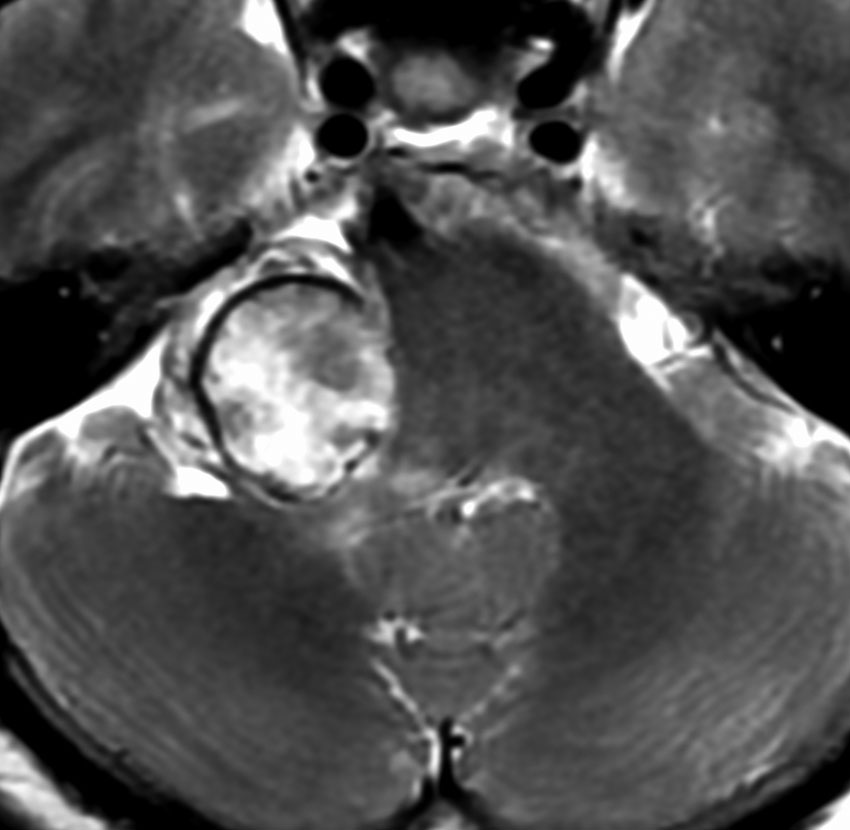

聴神経腫瘍でまず手術が必要なのは巨大なものです。この4枚の写真は私が実際に手術をした患者さんのものです。脳幹部という脳の最も大切なところが腫瘍によって圧迫されて変形しているのが特徴です。右上のものはのう胞性腫瘍なので大きさの割に手術のリスクは高くありませんが,左上のものは実質性で出血性のものですごくリスクが高い手術でした。左下のものは普通のリスク。右下のものは超高難易度のものです。

この腫瘍は脳幹部変形がとても強く,大きいので手術摘出するしか選択肢はありません

- 脳幹部の変形が高度な大きな腫瘍になると手術するしかありません

- 4cmを超えると危険だと考えてください